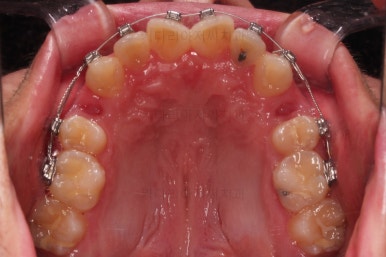

초진 시, 입안의 모습입니다.

치아를 모두 담기에 골격이 매우 작았어요.

이런 경우 치열이 ㅃ뚤어지거나 입이 튀어나오거나 뻐드렁니가 되거나 특정 치아가 묻혀버리거나 맨 뒤치아가 마치 사랑니처럼 올라오지 못한다거나 등등의 문제가 생기는데요.

이번 환자분은 전반적으로 삐뚠 상황이었어요.

앞니도 대칭적으로 삐뚤어져 흔히 나비치아라고 하는 형태로 보이고, 아랫니들은 U자 아치의 형태가 찌그러져 있네요.

당연히 교합도 맞지 않고요.

먼저 장치를 부착하고요.

환자분이 선택하신 장치는 자가결찰 메탈장치 입니다.